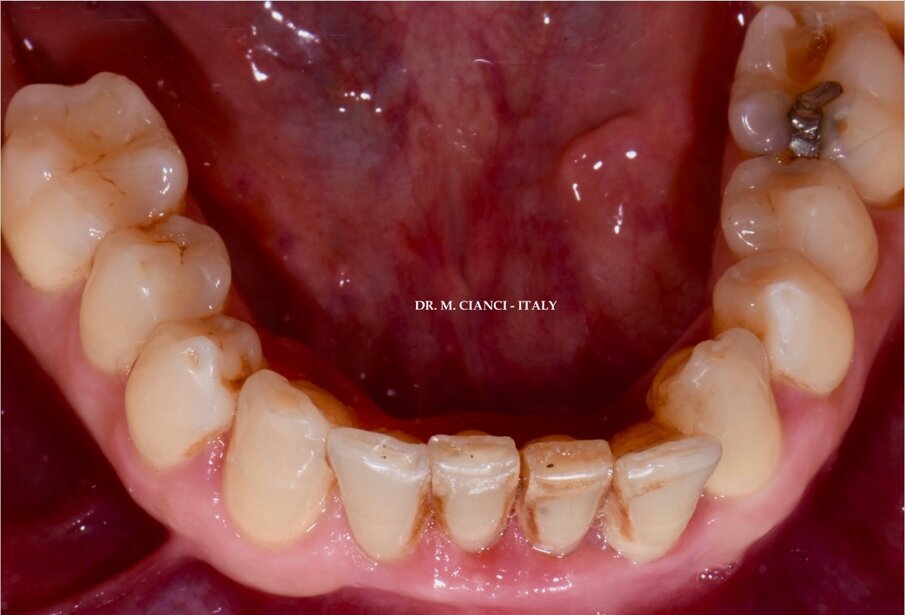

Il paziente, un uomo di 42 anni in buona salute generale e non fumatore, si presentava alla nostra osservazione presso IITS (International Implant Training School) nel febbraio 2020 lamentando difficoltà a masticare e grande mobilità in corrispondenza dei quattro incisivi inferiori (Fig. 1): l’esame TAC 3D Cone Beam evidenziava un grave riassorbimento osseo a pieno spessore da 3.2 a 4.2 con una perdita verticale di circa 14,3 mm (Fig. 2). Si decideva pertanto di procedere, una volta eseguiti tutti i trattamenti di igiene e profilassi, alla avulsione dei quattro incisivi inferiori con asportazione di ampio tessuto granulomatoso e contestuale posizionamento di un ponte provvisorio cementato tipo Maryland: un mese dopo abbiamo eseguito la rigenerazione guidata (GBR orizzontale e verticale) con innesto di materiale alloplastico di origine bovina in formato granulare (0,25-1 mm) misto a PRGF (Plasma Rich in Growth Factors), inserendo una membrana pericardica riassorbibile adeguatamente scolpita “a sella” sulla zona edentula rigenerata, riposizionando infine il lembo mucoperiosteo a ripristino della corretta anatomia del mascellare: un’ampia letteratura ha dimostrato come il plasma ricco in fattori di crescita sotto forma di concentrati piastrinici (membrane, gel e liquido) stimola e accelera la rigenerazione ossea ottenendo tempi di rigenerazione più brevi favorendo anche una guarigione più rapida dei tessuti molli2, 3 (Fig. 3).

Fig. 1 - Incisivi inferiori in visione occlusale.